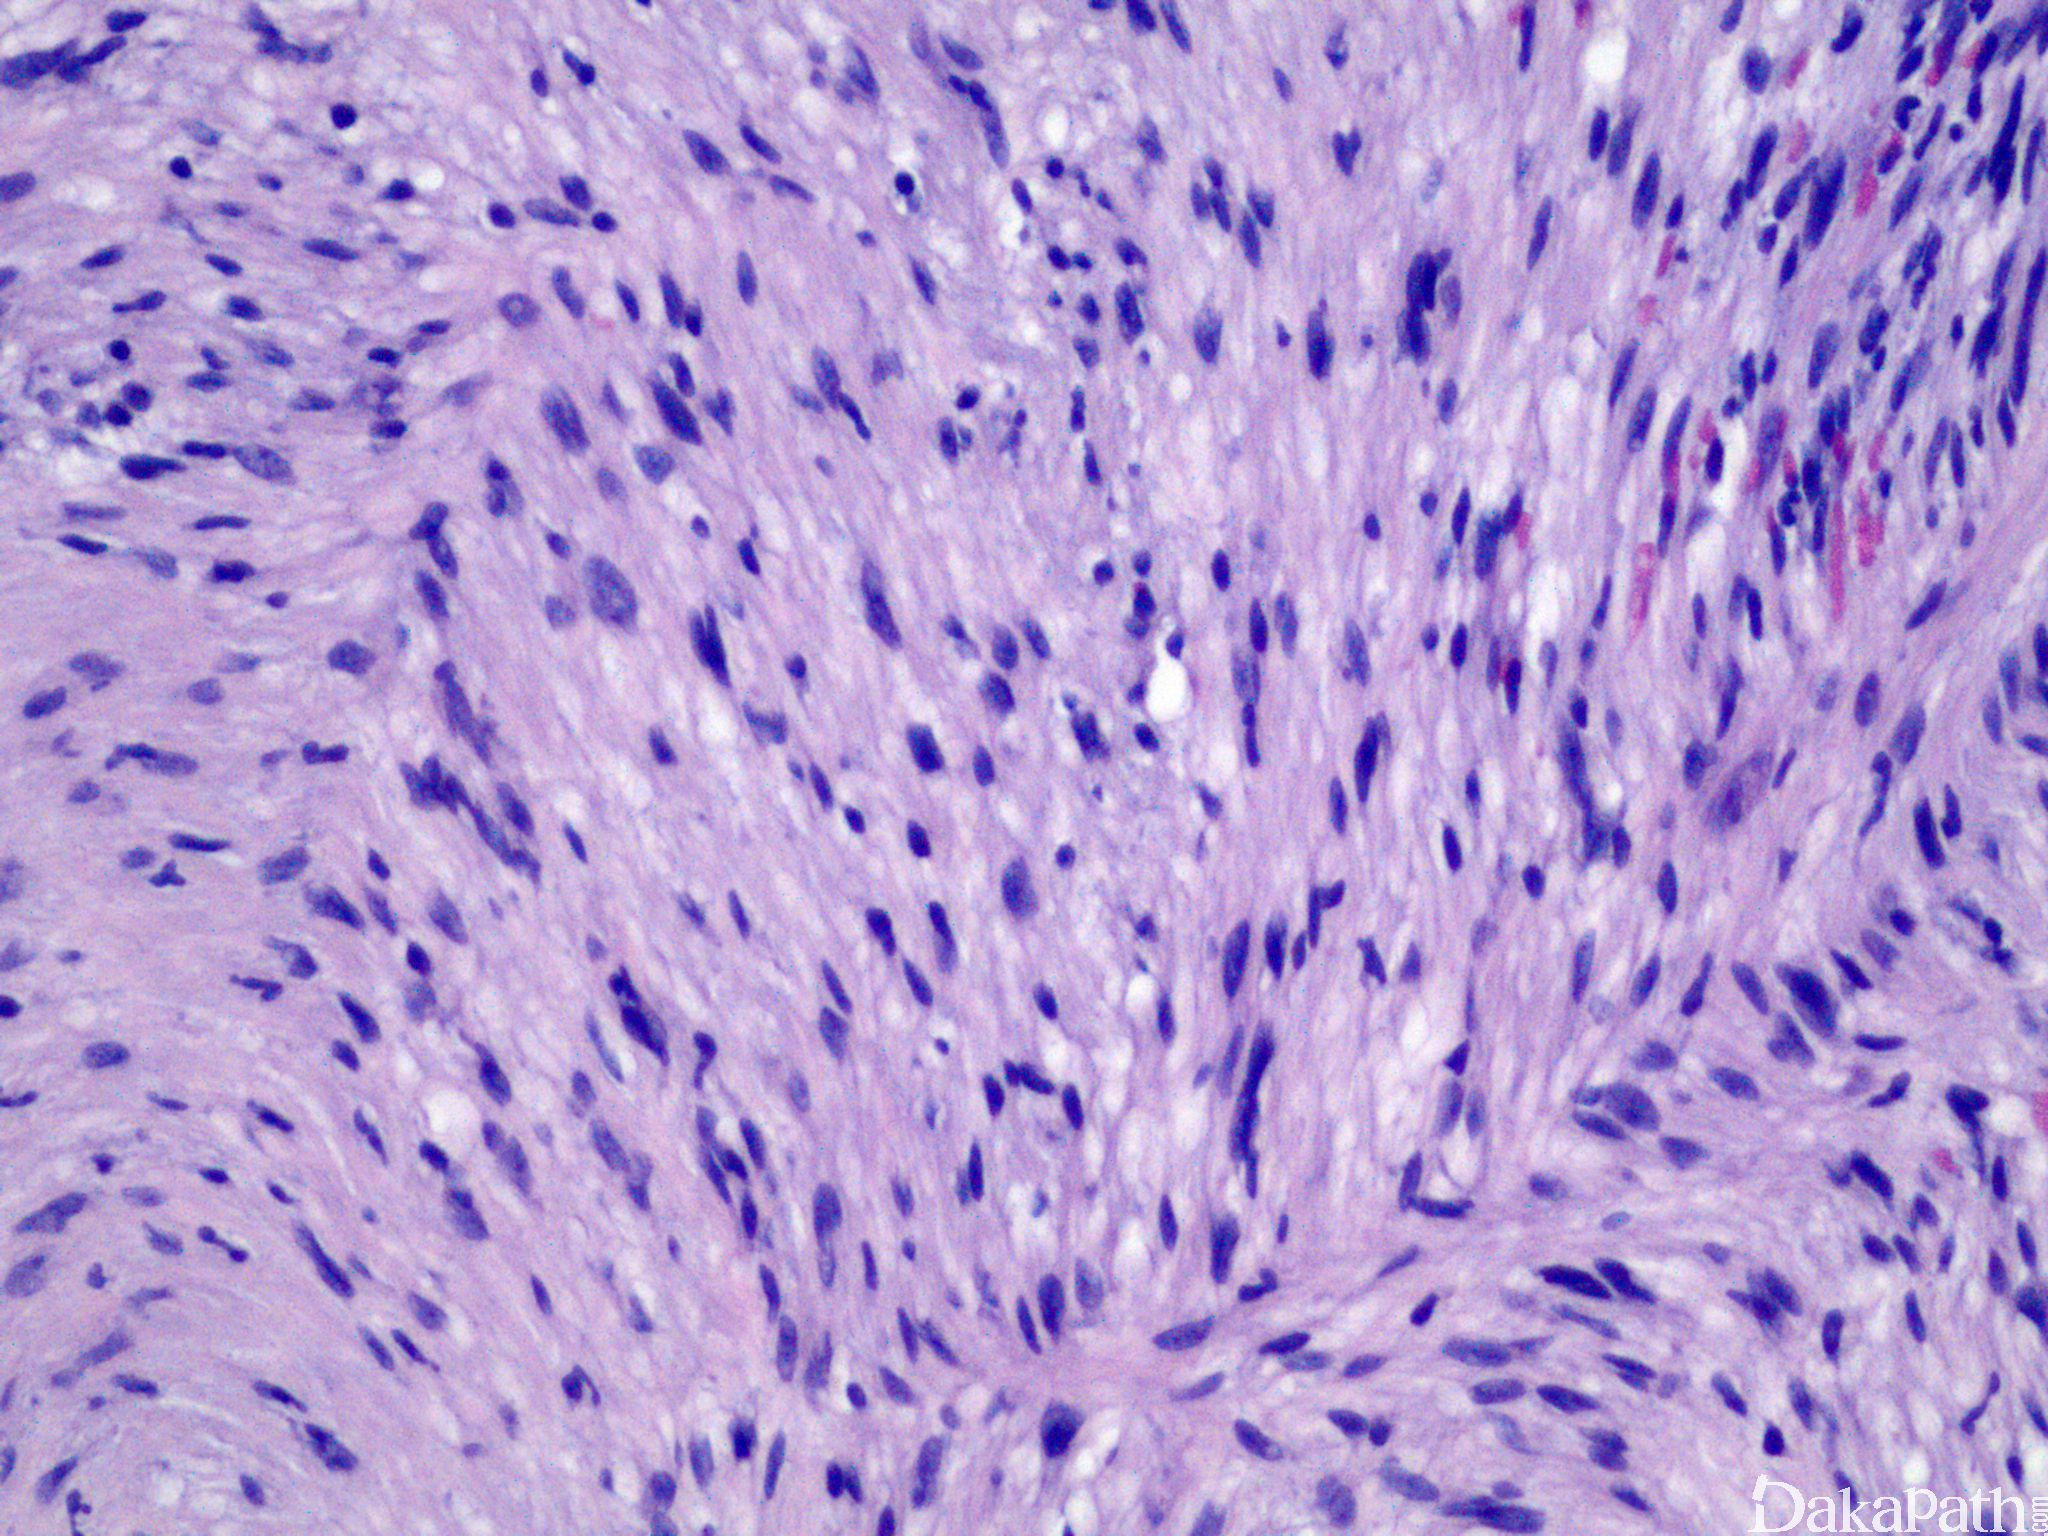

神经鞘瘤

schwannoma

肿瘤界限清楚, 周围有纤维性包膜。

肿瘤内有不同的分区:细胞富集区( Antoni A 区) 和细胞稀少区( Antoni B 区)交替分布

3. 特征性的 Verrocay 小体(呈栅栏状排列排列的细胞核)

4. 肿瘤细胞为梭形细胞,核呈波浪状。

5. 较大肿瘤肿瘤内常见厚壁血管。有点血管有玻璃样变

免疫组织化学染色:

S100, SOX-10 阳性